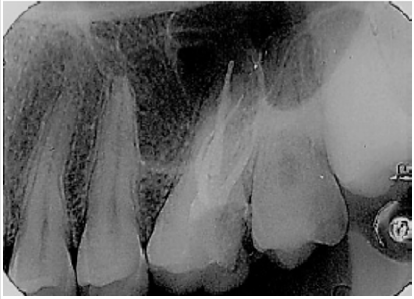

Patient, MCKS, female, 18 years old, went to Endodontic Specialization to treat the first left maxillary molar. After clinical and radiographic examination (Figure 1) the diagnostic was irreversible pulpitis. Anesthesia was performed with Mepiadre (DFL, Rio de Janeiro, Brazil) absolute isolation, coronary opening, location of channels, and working length was performed with apex locator (Romiapex A-15, Romidan Ltd, Kiryat Ono, Israel). The MB2 was localized using the # 0.10 C pilot file (VDW, Munich, Germany). Cervical preparation was performed with Protaper Universal SX instrument (DentisplyMailefer, Switzerland) and chemicalmechanical preparation with reciprocating Wave One Gold Primary instrumentation (Dentisply-Mailefer, Switzerland), irrigation with 2.5% sodium hypochlorite. The smear layer was removed and then an intracanal medication with calcium hydroxide paste was applied (SS WHITE, Rio de Janeiro, Brazil) and the teeth was sealed with Glass Ionomer (SS WHITE, Rio de Janeiro, Brazil). In the second appointment, the palatine root has been expanded with Wave One Gold Large (Dentisply-Maillefer, Switzerland), smear layer was removed and obturation performed (Figure 2).